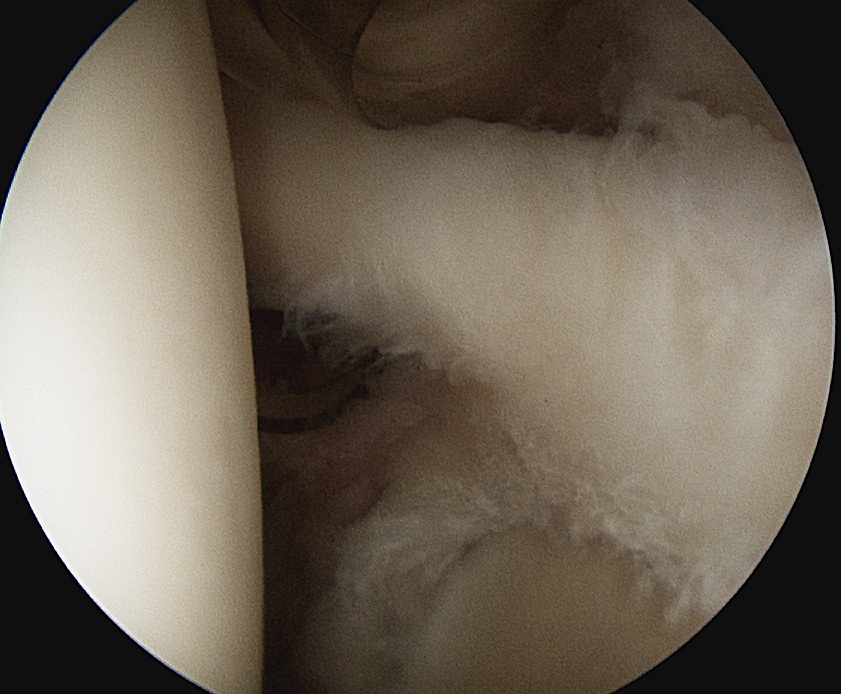

2. Prepare insertion

- shaver via anterior portal

- debride frayed labrum

- mobilise biceps tendon

- debride bony base to create ledge and bleeding bone